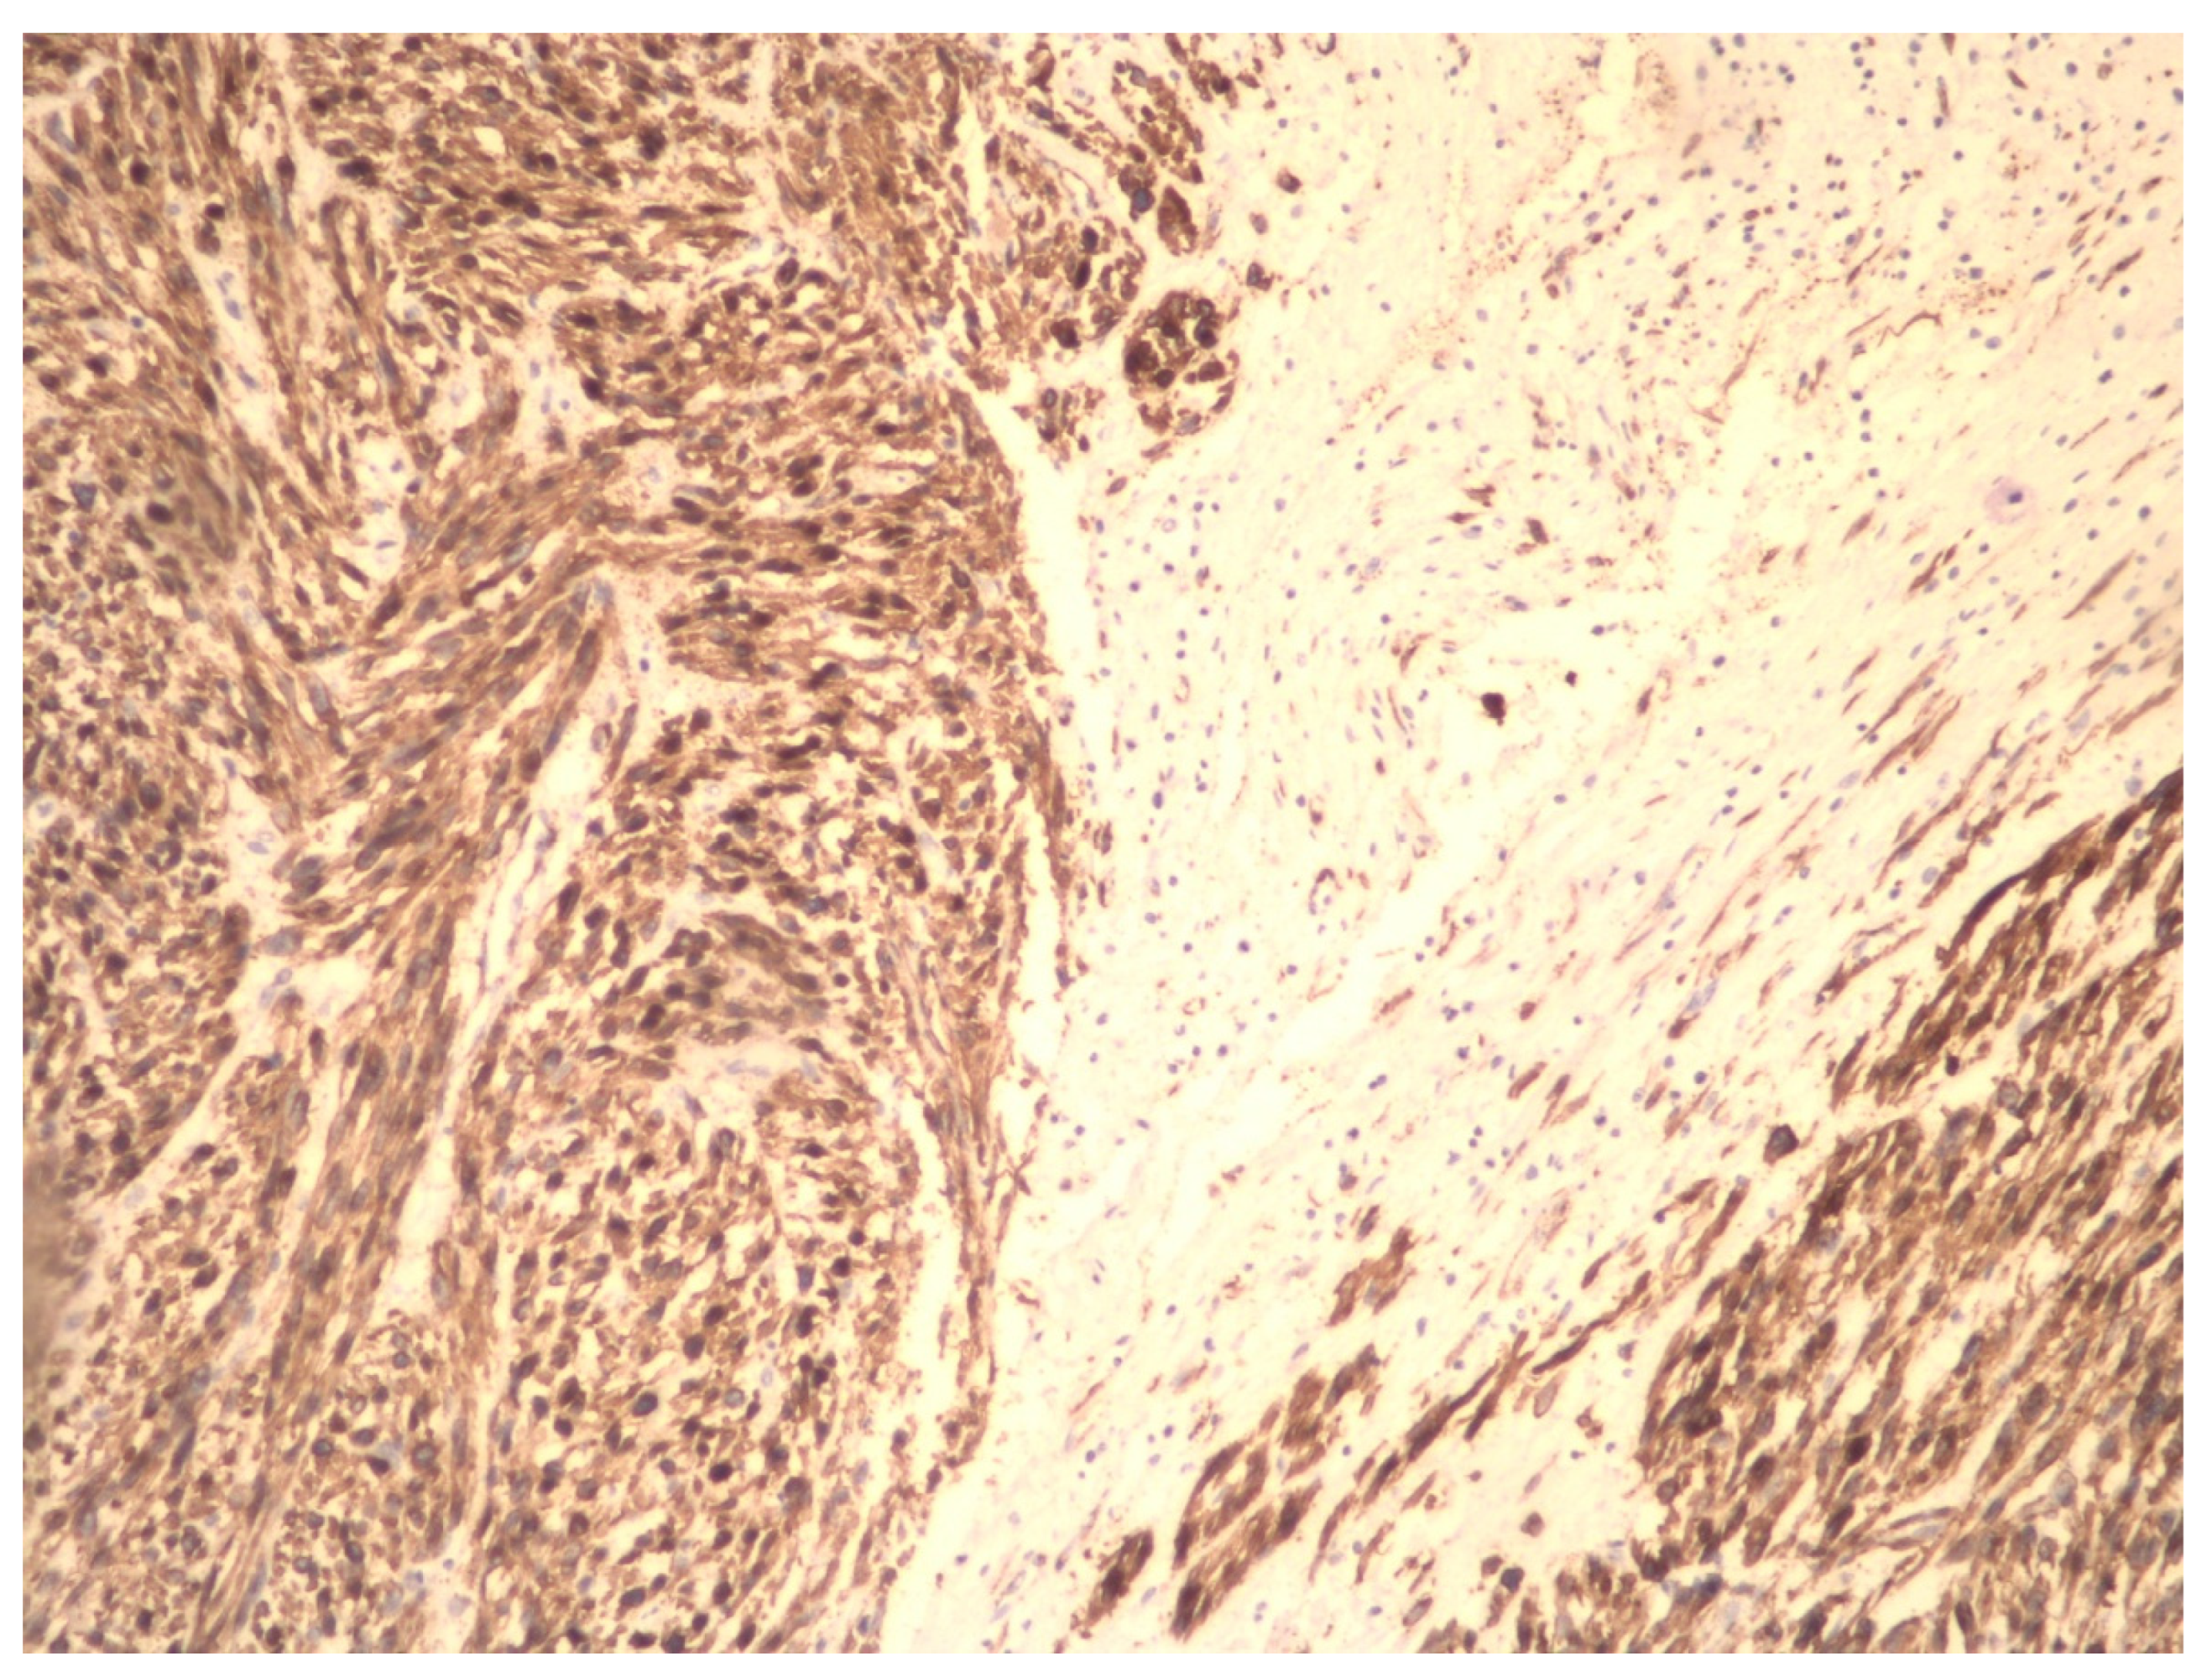

- Zhang, Q.; Kanis, M.J.; Ubago, J.; Liu, D.; Scholtens, D.M.; Strohl, A.E.; Lurain, J.R.; Shahabi, S.; Kong, B.; Wei, J.J. The selected biomarker analysis in 5 types of uterine smooth muscle tumors. Hum. Pathol. 2018, 76, 17–27. [Google Scholar] [CrossRef] [PubMed]